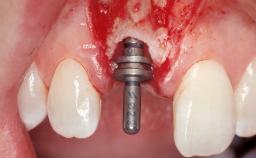

A 30-year-old female patient had lost tooth 21 and was referred to our clinic for consultation and treatment. Due to advanced apical infection, tooth 21 had been extracted two months earlier at another clinic and an acrylic-resin tooth had been bonded to the adjacent teeth. The patient desired implant treatment to avoid any damage to the adjacent natural teeth. While the patient had no history of any systemic disorder, she was a heavy smoker and exhibited medium to advanced periodontitis in the entire jaw. After the initial treatment to achieve a pocket probing depth of less than 4 mm and no bleeding on probing, a decrease in the height of the papillae mesial and distal to the extraction site and overall gingival recession were observed.

| Bone Augmentation | Horizontal|Staged |

| Augmentation Materials | Autogenous chips|Membrane |

| Soft Tissue Grafting | Simultaneous |